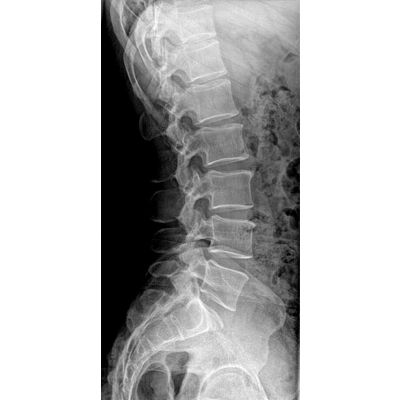

●探測(cè)器可以大范圍轉(zhuǎn)動(dòng),大尺寸有效探測(cè)面積,可滿足人體多部位攝影需求。